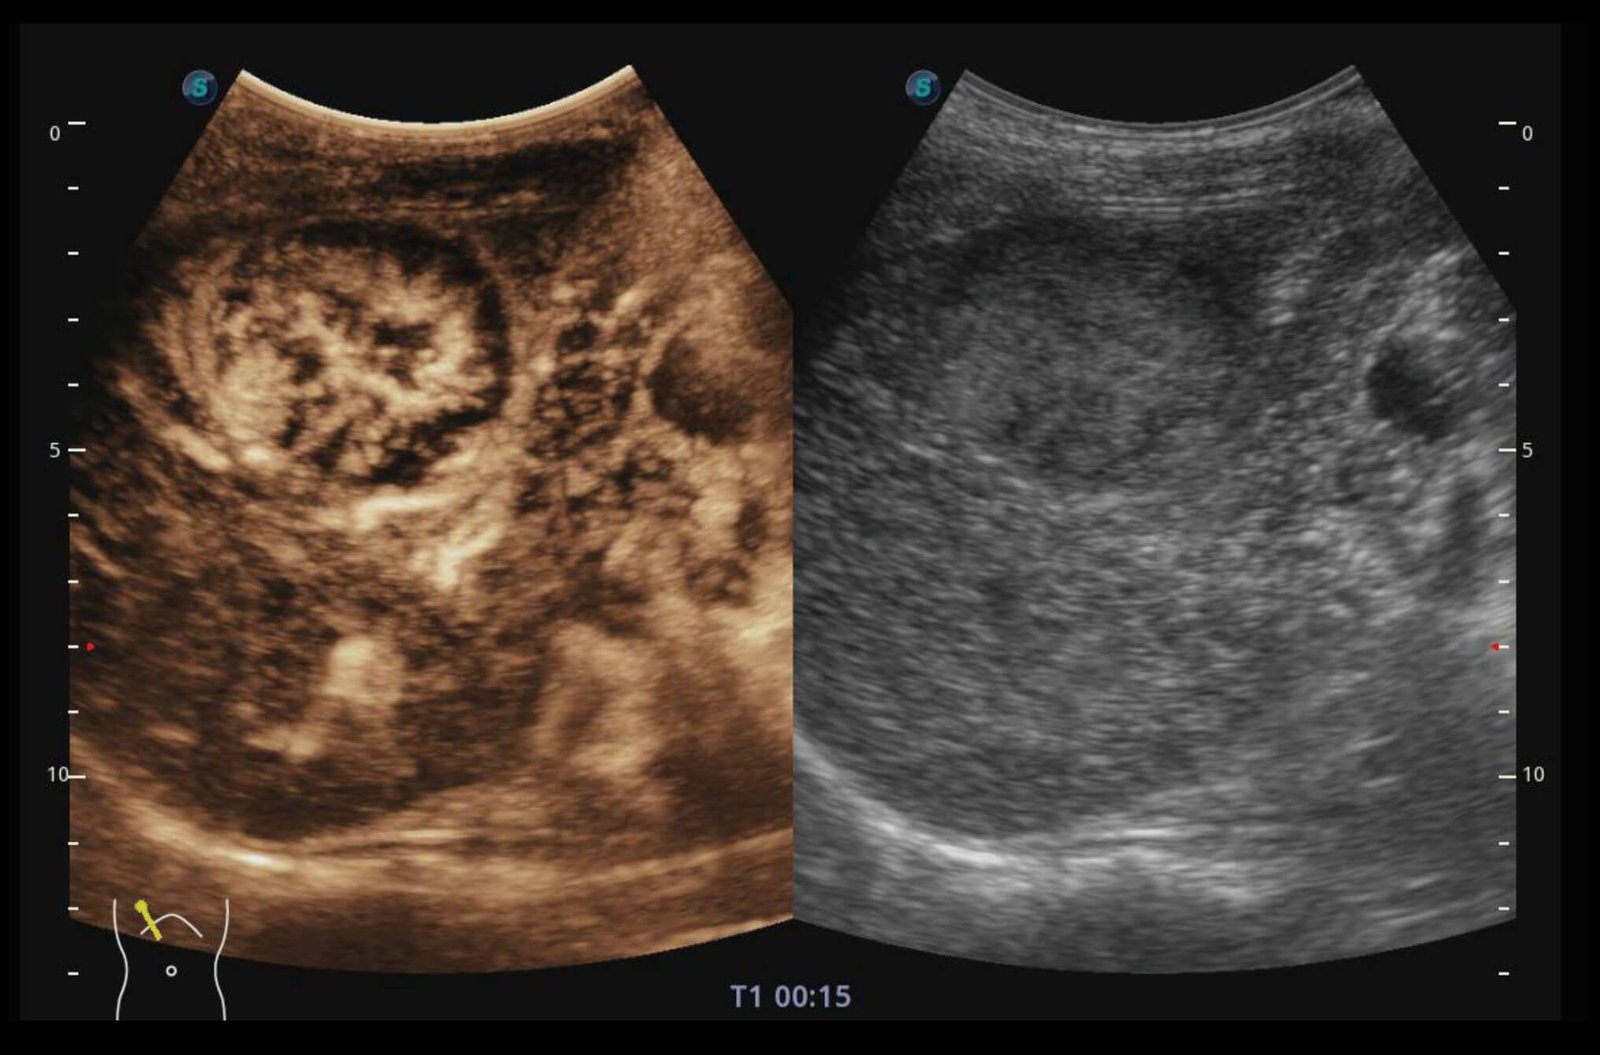

MScan+

Available for both B and 3D/4D modes, the new generation μScan+ provides you authentic presentation of details and lesion display through speckle reduction and enhanced border continuity.